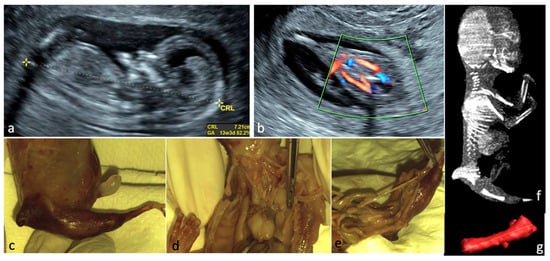

Figure 1. Sirenomelia. (a)—Sagittal view of the fetus at FT anomaly scan, showing normal profile, normal nuchal translucency, and present nasal bone. (b)—Single lower limb, pathognomonic aspect for sirenomelia, two femoral arteries seen. (ce)—Aspects from conventional autopsy: sagittal macroscopic view of the fetal pelvis, frontal view of the heart and great vessels (right lung removed), bilateral absent kidneys. (f)—CT scan, sagittal view of the fetus (CT scan performed after obtaining the autopsy data). (g)—Single femur measurements, Cone Beam CT technique used.

Figure 2. Defects of the upper limbs. (a,b)—Polydactyly at 16 weeks: US features—the supernumerary finger indicated by the red arrow and postbortum specimen. (c,d)—Clenched hands in a FADS case (Fetal Akinesia Deformation Sequence); the fetus had normal findings at the FT anomaly scan and developed limbs abnormalities toward the second trimester (US aspect in 3D surface rendering mode and postabortum specimen). (e,f)—Hypoplasia of the radius and ulna—(US aspect in 3D surface rendering mode and postabortum specimen); simultaneous oligodactyly may be appreciated in both images.

Figure 3. Limb-body wall complex. The abdominal organs in this fetus developed outside the body; the umbilical cord was absent; major limb deformities and severe scoliosis may be seen; given the fatal condition, the parents opted for termination of pregnancy. (a)—3D surface rendering applied at FT anomaly scan. (b)—postabortum specimen.